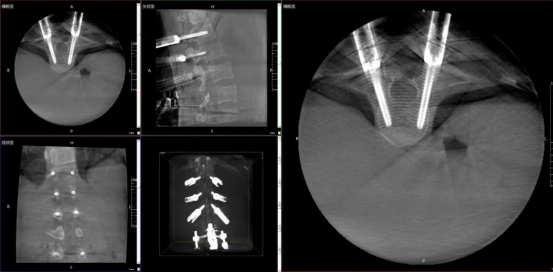

01 "X-ray Vision" — Intraoperative 3D Imaging

The 3D C-arm, also known as an "intraoperative CT," can generate cross-sectional, sagittal, and coronal images, as well as 3D volumetric reconstructions, providing more comprehensive and detailed anatomical information. It helps surgeons assess screw placement angles and fracture reduction, acting like the surgeon's "X-ray vision," making intraoperative procedures more precise and efficient.

02 Wide Field of View — See Everything

The device is equipped with a Large FPD, capable of capturing the entire lumbar spine, bilateral sacroiliac joints, and unilateral pelvis in a single scan. This avoids repeated adjustments by the operator due to limited FOV, improving workflow efficiency and reducing radiation exposure from multiple scans.